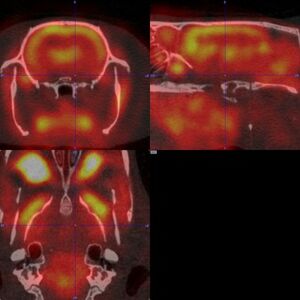

PET and MR in Mouse MetastaticTumor Model

(Left) Coronal whole-body PET/MR. (Right) Focused Axial PET/MR revealing location of lung and abdominal tumors.

Courtesy of Acknowledgements. Thanks to the Katherine Tucker, Mikayla Rodger, Dr. Lixin Ma, Dr. Carolyn Anderson, and Dr. Barry Edwards, MITC – Molecular & Imaging Theranostics Center, University of Missouri.